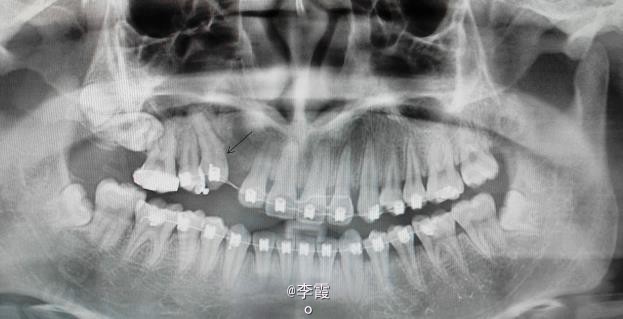

诊断:(1)13含牙囊肿(2)14高位垂直阻生。(3)17高位水平阻生。处理:(1)建议手术拔除15及去除13牙冠周围牙囊,保留13。(2)半年后做13和15正畸牵引。17暂时不做处理。

效果良好,患者满意。